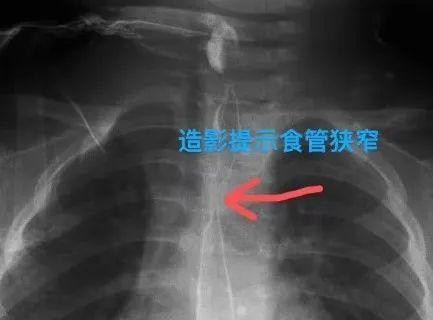

“厨房去污剂”是家里常备的清洁帮手,但是,稍有不慎,它们也可能给孩子的健康带来隐患。最近,1岁2个月的萌萌(化名)就因为误食“厨房去污剂”食道被“烧”成3毫米窄,真···